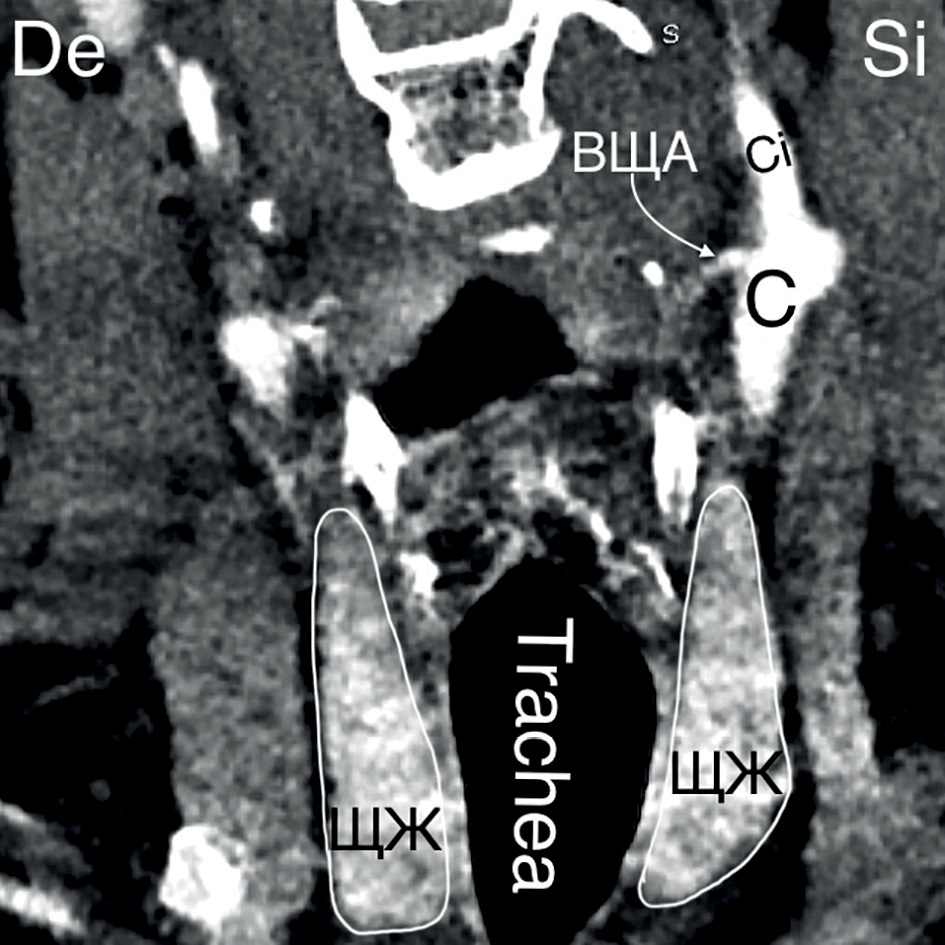

10. Рисунок 10. Источник ВЩА. А — КТ-ангиография (сагиттальный срез). Источником ВЩА является бифуркация общей сонной артерии; Б — КТ-ангиография (горизонтальный срез). ВЩА берет начало от наружной сонной артерии. C — a. carotis communis; Ce — a. carotis externa; Ci — a. carotis interna. | |